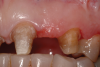

A patient presented with two defective 3-unit fixed partial dentures spanning teeth Nos. 6 through 8 and teeth Nos. 9 through 11 (Figure 7). The defective fixed partial dentures were removed (Figure 8), an impression was made, and traditional provisional fixed partial dentures without ovate pontics were placed. After the impression was sent to the laboratory, the lab technician prepared ovate pontic sites on the stone cast (Figure 9) and fabricated the new definitive bridges. On the day of insertion, the provisional fixed partial dentures were removed (Figure 10), ovate pontic sites were prepared using a teardrop-shaped diamond bur (Figure 11), and the sites were sounded to confirm that there was at least 2 mm from the base of the pontic site to the alveolar bone (Figure 12). The fixed partial dentures were cemented, and the postoperative healing was uneventful (Figure 13).